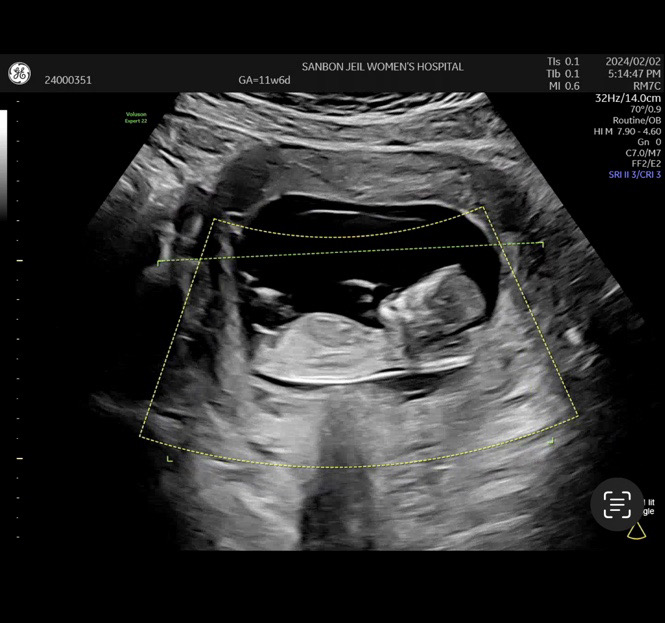

12주차 각도법..

애아빤 딸같다고 하고 전 아들같고 ㅎㅎ 잘 보시는분!!